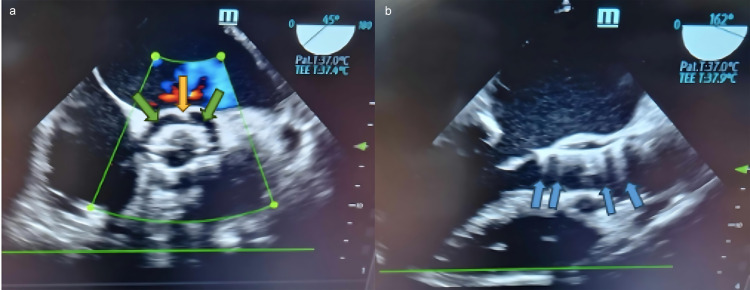

Transcatheter aortic valve implantation (TAVI) is a minimally invasive procedure to treat severe aortic stenosis in select patients. Patients who have undergone TAVI are at high risk of infective endocarditis (IE), especially during the first year post-operation. Early diagnosis of IE is essential to initiate targeted antibiotic therapy and/or surgical intervention. However, the early detection of IE following TAVI poses significant diagnostic challenges. Current imaging techniques, including echocardiography, nuclear imaging, and magnetic resonance imaging, have varying degrees of sensitivity and specificity, each with inherent limitations. Nuclear imaging modalities, such as positron emission tomography/computed tomography using 18F-fluorodeoxyglucose (18F-FDG PET/CT) and white blood cell single photon emission computed tomography/computed tomography (WBC SPECT/CT), have shown promise in early IE detection, particularly due to the ability of these methods to identify metabolic and anatomical abnormalities. However, false-positive results related to post-operative inflammation complicate data interpretation, and limited data exist for using these methods in very early IE detection post-TAVI. Intracardiac echocardiography (ICE) offers enhanced visualization of prosthetic valve leaflets, but the invasive nature of ICE restricts its widespread use. Whole-body imaging, such as 18F-FDG PET/CT, facilitates the identification of distant lesions and systemic complications, aiding diagnosis and treatment decisions. Diagnosing IE after TAVI is especially challenging within the first 60 days post-procedure, a critical period when imaging findings may be inconclusive due to false negatives or limited availability of advanced modalities. This review underscores the diagnostic complexity of very early and early (0-60 days) IE post-TAVI, emphasizing the need for a multimodal imaging approach to overcome the limitations of individual modalities. Nonetheless, early antimicrobial therapy should be considered even without definitive imaging findings, highlighting the importance of clinical vigilance in managing this challenging condition.